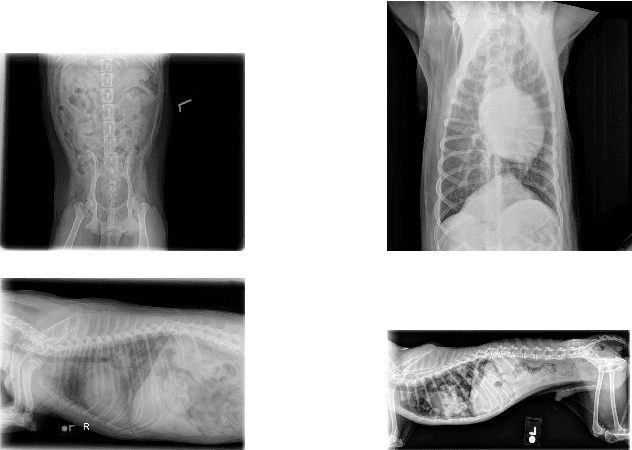

Abstract:Self-supervised learning has emerged as a powerful paradigm for training deep neural networks, particularly in medical imaging where labeled data is scarce. While current approaches typically rely on synthetic augmentations of single images, we propose VET-DINO, a framework that leverages a unique characteristic of medical imaging: the availability of multiple standardized views from the same study. Using a series of clinical veterinary radiographs from the same patient study, we enable models to learn view-invariant anatomical structures and develop an implied 3D understanding from 2D projections. We demonstrate our approach on a dataset of 5 million veterinary radiographs from 668,000 canine studies. Through extensive experimentation, including view synthesis and downstream task performance, we show that learning from real multi-view pairs leads to superior anatomical understanding compared to purely synthetic augmentations. VET-DINO achieves state-of-the-art performance on various veterinary imaging tasks. Our work establishes a new paradigm for self-supervised learning in medical imaging that leverages domain-specific properties rather than merely adapting natural image techniques.

Abstract:This work describes the development and real-world deployment of a deep learning-based AI system for evaluating canine and feline radiographs across a broad range of findings and abnormalities. We describe a new semi-supervised learning approach that combines NLP-derived labels with self-supervised training leveraging more than 2.5 million x-ray images. Finally we describe the clinical deployment of the model including system architecture, real-time performance evaluation and data drift detection.